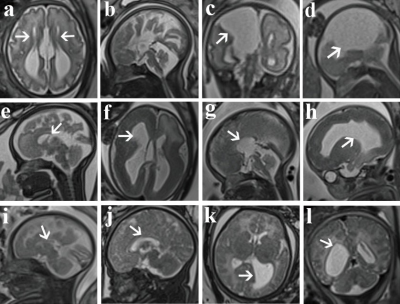

Fig. 2. a-b, A fetus at 33 weeks of gestation with isolated complete absence of the corpus callosum (CACC). c-d A fetus at 30 weeks of gestation. CACC with a huge intra-hemispheric cyst. e, A fetus at 32 weeks of gestation with isolated splenium absence (PACC). f-h A fetus at 33 weeks of gestation. A partial absence of the CC (PACC) with pachygyria, and left front lobe leukodystrophy. i, A fetus at 28 weeks of gestation with isolated hypogenesis (HCC) and the CC is significantly thinner and shorter. J-l A fetus at 35 weeks of gestation. HCC with bilateral frontal lobe leukodystrophy.